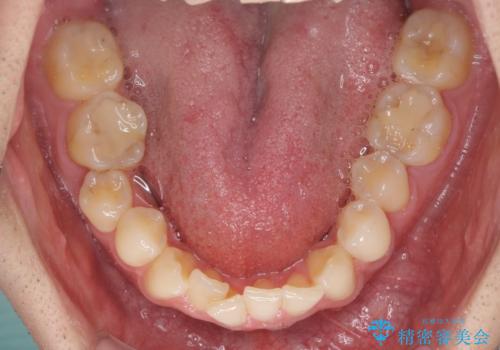

ディープバイトと叢生 インビザラインによる矯正治療

- 前歯のディープバイトと叢生を気にして来院された患者様です。

上下ともに叢生が認められたため、親知らずすべてを抜歯し、歯列全体を後方へ移動させることで歯列を整えることとしました。

ディープバイトもデコボコも改善され、気になっていた銀歯もセラミックとなり、患者様には大変満足していただきました。